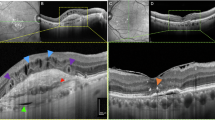

a Representative late phase fundus fluorescein angiography (FFA) images at indicated time points post laser injury. Scale bar: 200 µm. b Quantification of vascular leakage intensity after laser-induced CNV. 3 d n = 85; 7 d n = 36; and 14 d n = 22 retinas from individual mice. FA fluorescein angiography. c Quantification of vascular leakage area after laser-induced CNV. DMSO/XBD173 3 d n = 91/79; 7 d n = 42/33; 14 d n = 30 retinas from individual mice. d Representative laser-induced CNV stained with isolectin B4 in RPE/choroidal flat mounts. Scale bar: 100 µm; e Quantification of laser-induced CNV area in RPE/choroidal flat mounts. n = 22 RPE/choroids from individual mice. f Pro-angiogenic growth factor levels in retinas of naïve and lasered TSPOfl/fl and TSPOΔMG mice at indicated time points. n = 8 retinas/RPEs from individual mice. g Pro-angiogenic growth factor levels in RPE/choroids of naïve and lasered TSPOfl/fl and TSPOΔMG mice at indicated time points. n = 8 retinas/RPEs from individual mice. h Representative infrared (IR) fundus images at indicated time points post laser injury. Lower panel shows OCT scan from one laser spot marked by a red line. Scale bar: 200 µm. i Quantification of laser spot size. 0 d n = 45, 3 d n = 39, 7 d n = 33, and 14 d n = 25 eyes from individual mice. Data show mean ± SEM and a linear mixed model was used for statistical analyses; *P < 0.05; **P < 0.01; and ***P ≤ 0.001. n.s., not significant. Source data are provided as a Source Data file.

a Representative late phase fundus fluorescein angiography (FFA) images at indicated time points post laser injury. Scale bar: 200 µm. b Quantification of vascular leakage intensity after laser-induced CNV. 3 d n = 56; 7 d, 14 d n = 25 eyes from individual mice. c Quantification of vascular leakage area after laser-induced CNV. 3 d n = 56; 7 d, 14 d n = 25 eyes from individual mice. d Representative laser-induced CNV stained with isolectin B4 in RPE/choroidal flat mounts. Scale bar: 100 µm; FA fluorescein angiography. e Quantification of laser-induced CNV area in RPE/choroidal flat mounts. DMSO/XBD173 3 d n = 18/34; 7 d n = 38/17; 14 d n = 17/23 RPE/choroids from individual mice. f Pro-angiogenic growth factor levels in retinas of naïve and lasered mice at indicated time points. n = 8 eyes from individual mice. g Pro-angiogenic growth factor levels in RPE/choroids of naïve and lasered mice at indicated time points. n = 8 eyes from individual mice. h Representative infrared (IR) fundus images at indicated time points post laser injury. Lower panel shows OCT scan from one laser spot marked by a red line. Scale bar: 200 µm. I Quantification of laser spot size. DMSO/XBD173 0 d n = 106/71; 3 d n = 72/42; 7 d, 14 d n = 26 eyes from individual mice. Data show mean ± SEM and a linear mixed model was used for statistical analyses; *P < 0.05; **P < 0.01; and ***P ≤ 0.001. n.s., not significant. Source data are provided as a Source Data file.

a Representative late phase fundus fluorescein angiography (FFA) images at indicated time points post laser injury. Scale bar: 200 µm. b Quantification of vascular leakage intensity after laser-induced CNV. 3 d/7 d n = 32 and 14 d n = 22 eyes from individual mice. c Quantification of vascular leakage area after laser-induced CNV. 3 d/7 d n = 32 and 14 d n = 22 eyes from individual mice. d Representative laser-induced CNV stained with isolectin B4 in RPE/choroidal flat mounts. Scale bar: 100 µm; FA fluorescein angiography. e Quantification of laser-induced CNV area in RPE/choroidal flat mounts. WT/Nox1-KO n = 12/18 RPE/choroids from individual mice. f Pro-angiogenic growth factor levels in retinas of naïve and lasered WT and Nox1-KO mice at indicated time points. n = 8 eyes from individual mice. g Pro-angiogenic growth factor levels in RPE/choroids of naïve and lasered WT and Nox1-KO mice at indicated time points. n = 8 eyes from individual mice. h Representative infrared (IR) fundus images at indicated time points post laser injury. Lower panel shows OCT scan from one laser spot marked by a red line. Scale bar: 200 µm. I Quantification of laser spot size. WT/Nox1-KO 0 d n = 28/68, 3 d n = 22/51, 7 d n = 22/45,14 d n = 22/25, n = 25 eyes from individual mice. Data show mean ± SEM. A linear mixed model was used for statistical analyses, *P < 0.05; **P < 0.01; and ***P ≤ 0.001. n.s., not significant. Source data are provided as a Source Data file.